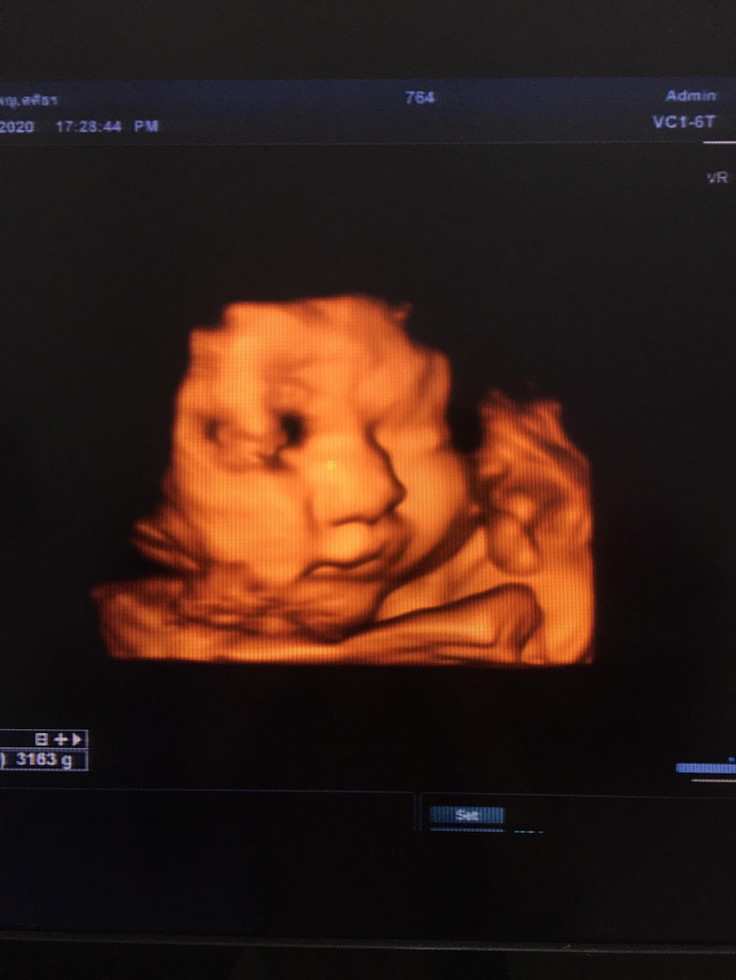

กำหนดคลอด17นี้ค่ะ

38w แล้วค่ะพร้อมแตกแล้ว

ใกล้จะเจอกันแล้วจ้าา